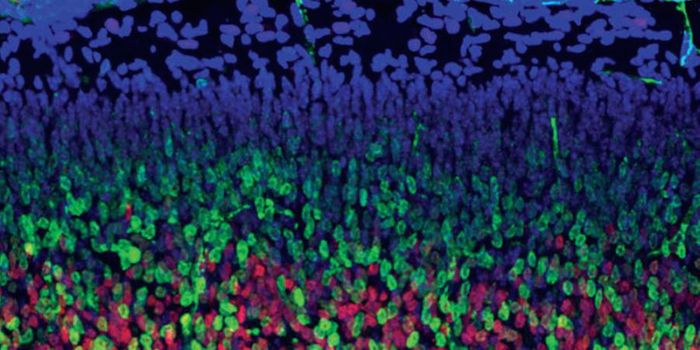

APR 01, 2015NeuroscienceComplex brain disorders, such as autism or schizophrenia, still puzzle scientists because their causes lie hidden in ear ...

JUN 01, 2015NeuroscienceThere are a few essential ways to understand the neural workings of the human brain. One is to painstakingly map the cir ...